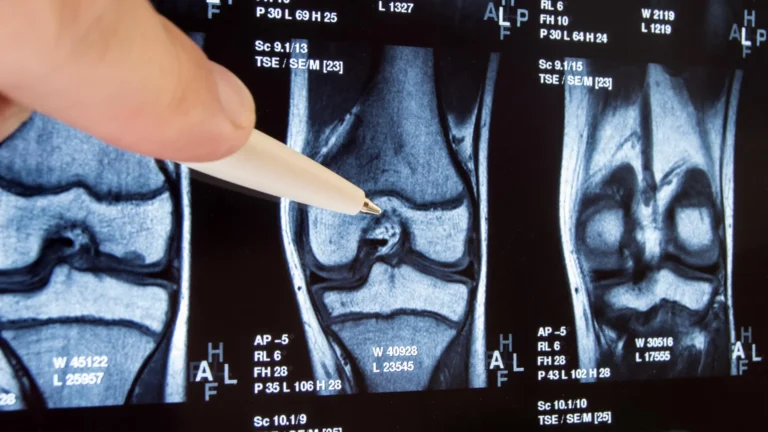

To address this crucial void, a team of researchers embarked on an ambitious project: an "umbrella" systematic review. This rigorous methodology involves synthesizing findings from multiple existing systematic reviews and randomized clinical trials (RCTs), offering the highest level of evidence in the hierarchy of medical research. By casting a wide net across major research databases for studies published through November 2025, the team meticulously gathered and analyzed data. Their final analysis incorporated a substantial body of evidence, including five systematic reviews encompassing 8,631 participants and 28 individual randomized clinical trials involving 4,360 participants. The studies focused on various joint locations, with the majority (23) addressing knee or hip osteoarthritis, three on hand osteoarthritis, and two on ankle osteoarthritis. This extensive dataset allowed for a robust investigation into the comparative effectiveness of exercise therapy.